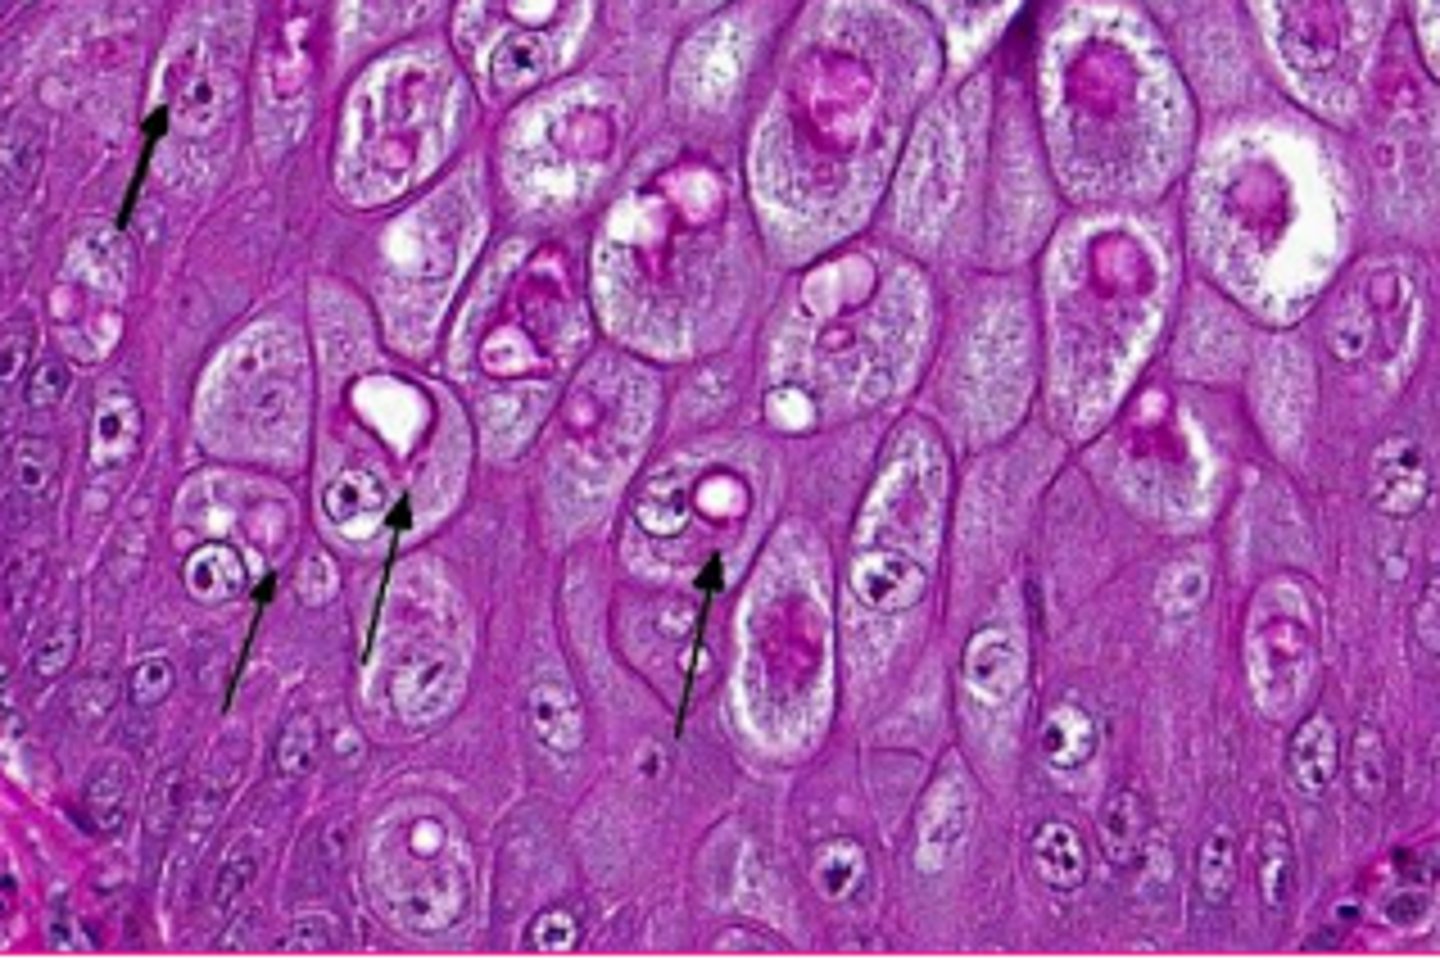

glycogen or lipid?

glycogen

spiderwork webbing of cytoplas, and central nucleus

<p>glycogen</p><p>spiderwork webbing of cytoplas, and central nucleus</p>

28

New cards

lipid

displaced nuclei,

<p>lipid</p><p>displaced nuclei,</p>

29

central nuclei, some webbing

<p>glycogen</p><p>central nuclei, some webbing</p>

what is this?

viral inclusions

<p>viral inclusions</p>